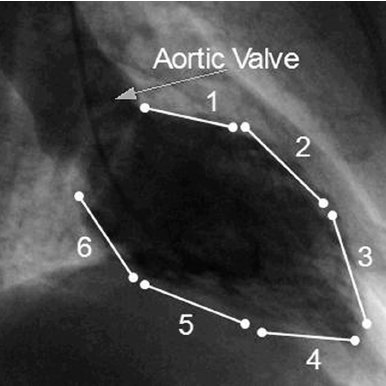

This is known as Stress cardiomyopathy (SCMP) in medical language: A heart condition that arises out of extreme emotional stress. The apex of our heart balloons out as the heart pumps and tries to squeeze the blood inside it out into our body. The ventricle instead balloons out so that no blood goes out of heart. The heart fails in the process. This leads to failure of heart, breathing difficulties and swelling of body of the patient. Most of the weak hearted persons land in this state.

The ballooning of apex of our left heart resembles a Takotsubo.

Tako-tsubo is an ancient Japanese device to trap octopuses in the sea. (See pic)

As our heart resembles exactly like a Takotsubo, it is known as Takotsubo Cardiomyopathy.